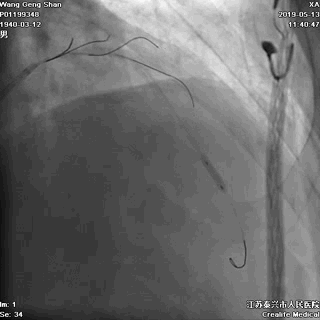

06 LM-LAD支架后扩张

交换回旋支导丝,非顺应性球囊顺序高压扩张

07 LM支架近段优化(POT)

左主干近段用大一号非顺应性球囊行高压扩张

IVUS评估,支架贴壁良好。